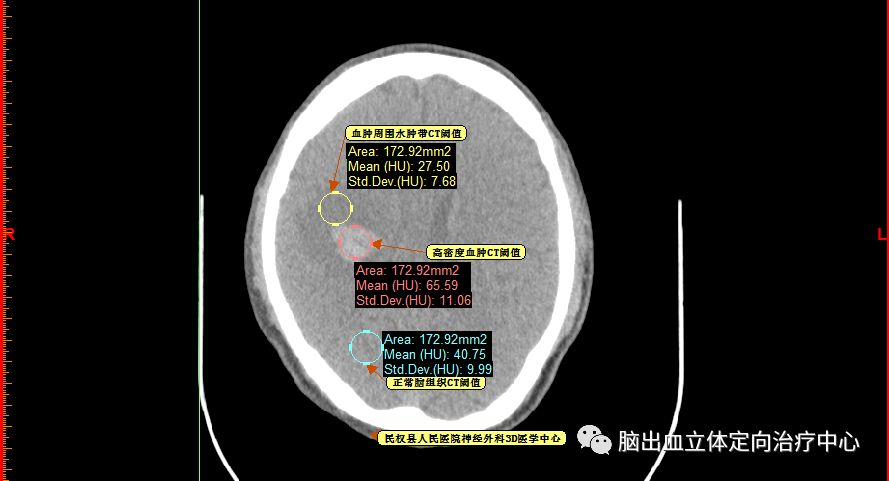

测量各密度区域CT阈值,可见高密度区域(红色区域)CT阈值为60.66,低密度区域(蓝色区域)CT阈值为44.39,正常脑组织区域CT阈值为20.94。

再仔细观察并划定血肿分层区域,可设定血肿为高密度区域、低密度区域,和正常脑组织对比

以红色区域划分为高密度区域、蓝色区域划分为低密度区域